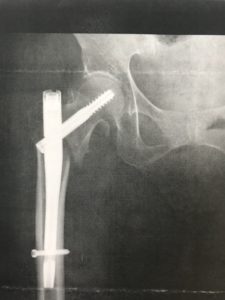

整復後―内側骨皮質 症例②

では次の症例です。この症例は整復後画像のみですが、少し内側骨皮質を見てみましょう。

いかがでしょうか?症例➀と比較すると、著しく内側骨皮質がズレているのが分かると思います。明らかに【大腿骨転子部骨折不安定型】だと分かりますね。

これだと、荷重をかけようにもラインがズレているので、跛行・痛みは免れないと予測できます。

ただ、荷重による骨癒合により徐々に荷重はのってくるのを期待し、転位を進行させない様に、適荷重を負荷することが非常に重要となります。